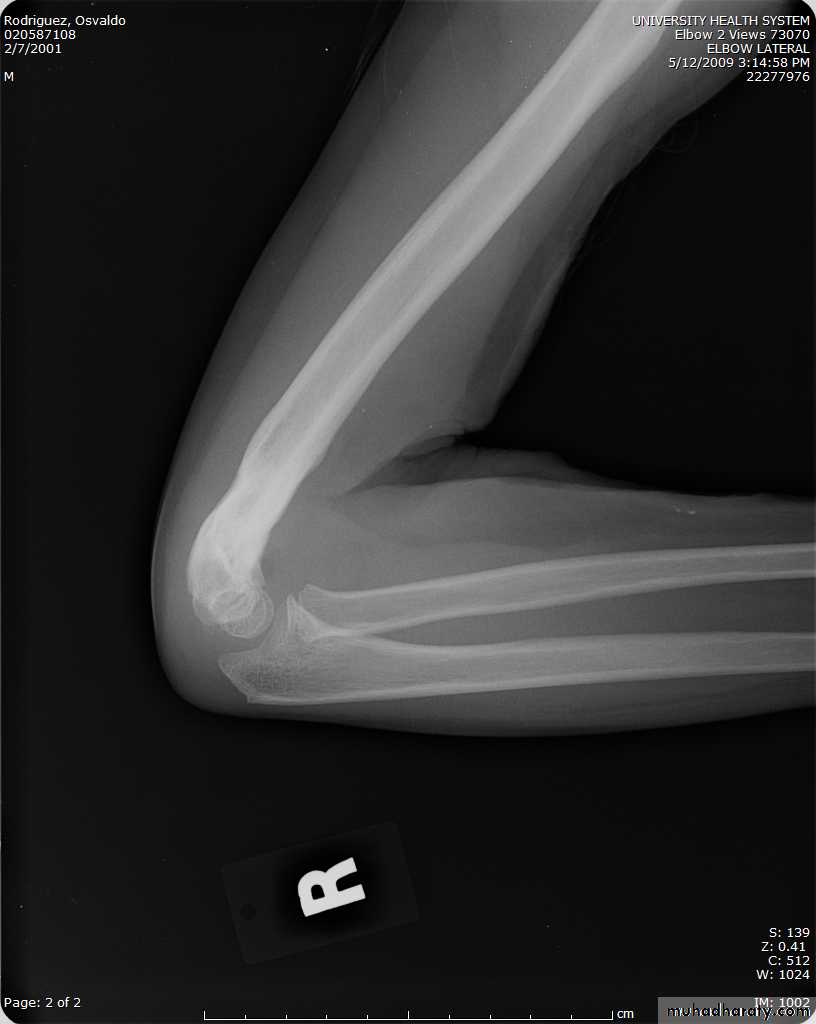

What type of supracondylar fracture

does this patient have?Flex

ionHow do the flexion patterns present?